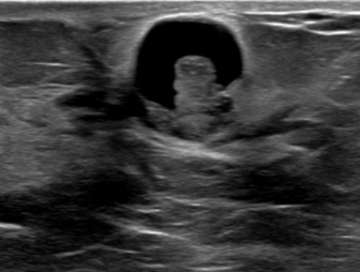

Well-circumscribed, anechoic, parallel, and avascular tubular structure with well-defined borders

The ultrasound above demonstrates a well-circumscribed, anechoic, parallel, and avascular tubular structure with well-defined borders, consistent with a dilated duct. The opposite breast also revealed similar dilation of the ducts, this symmetry is reassuring and benign. Features of ductal dilation which are concerning (and may warrant biopsy) include unilateral breast ductal dilation or a focal ductal dilation in a breast with otherwise normal sized ducts. Furthermore, a dilated duct which is not anechoic (fluid filled or with internal soft tissue nodularity), with an irregular shape, or with indistinct margins are also more suspicious.